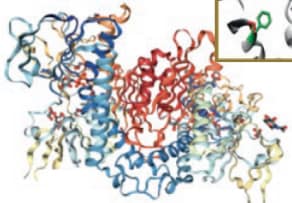

Protein carbonylation is detected and quantified with 2D-oxyDIGE, a novel proteomic approach using specific fluorescent cyanine dyes coupled with hydrazide probes which will react with protein carbonyls.

SOD-1 protein, an antioxidant protein, will be used to measure carbonylation. A panel of different mutations of the SOD-1 protein involved in ALS disease (amyotrophic lateral sclerosis) will be studied and assessed for their susceptibility to carbonylation and to form aggregates.

In order to improve the specificity and the sensitivity of the technique, nanocluster probes are under development to replace theses cy-hydrazide dyes.